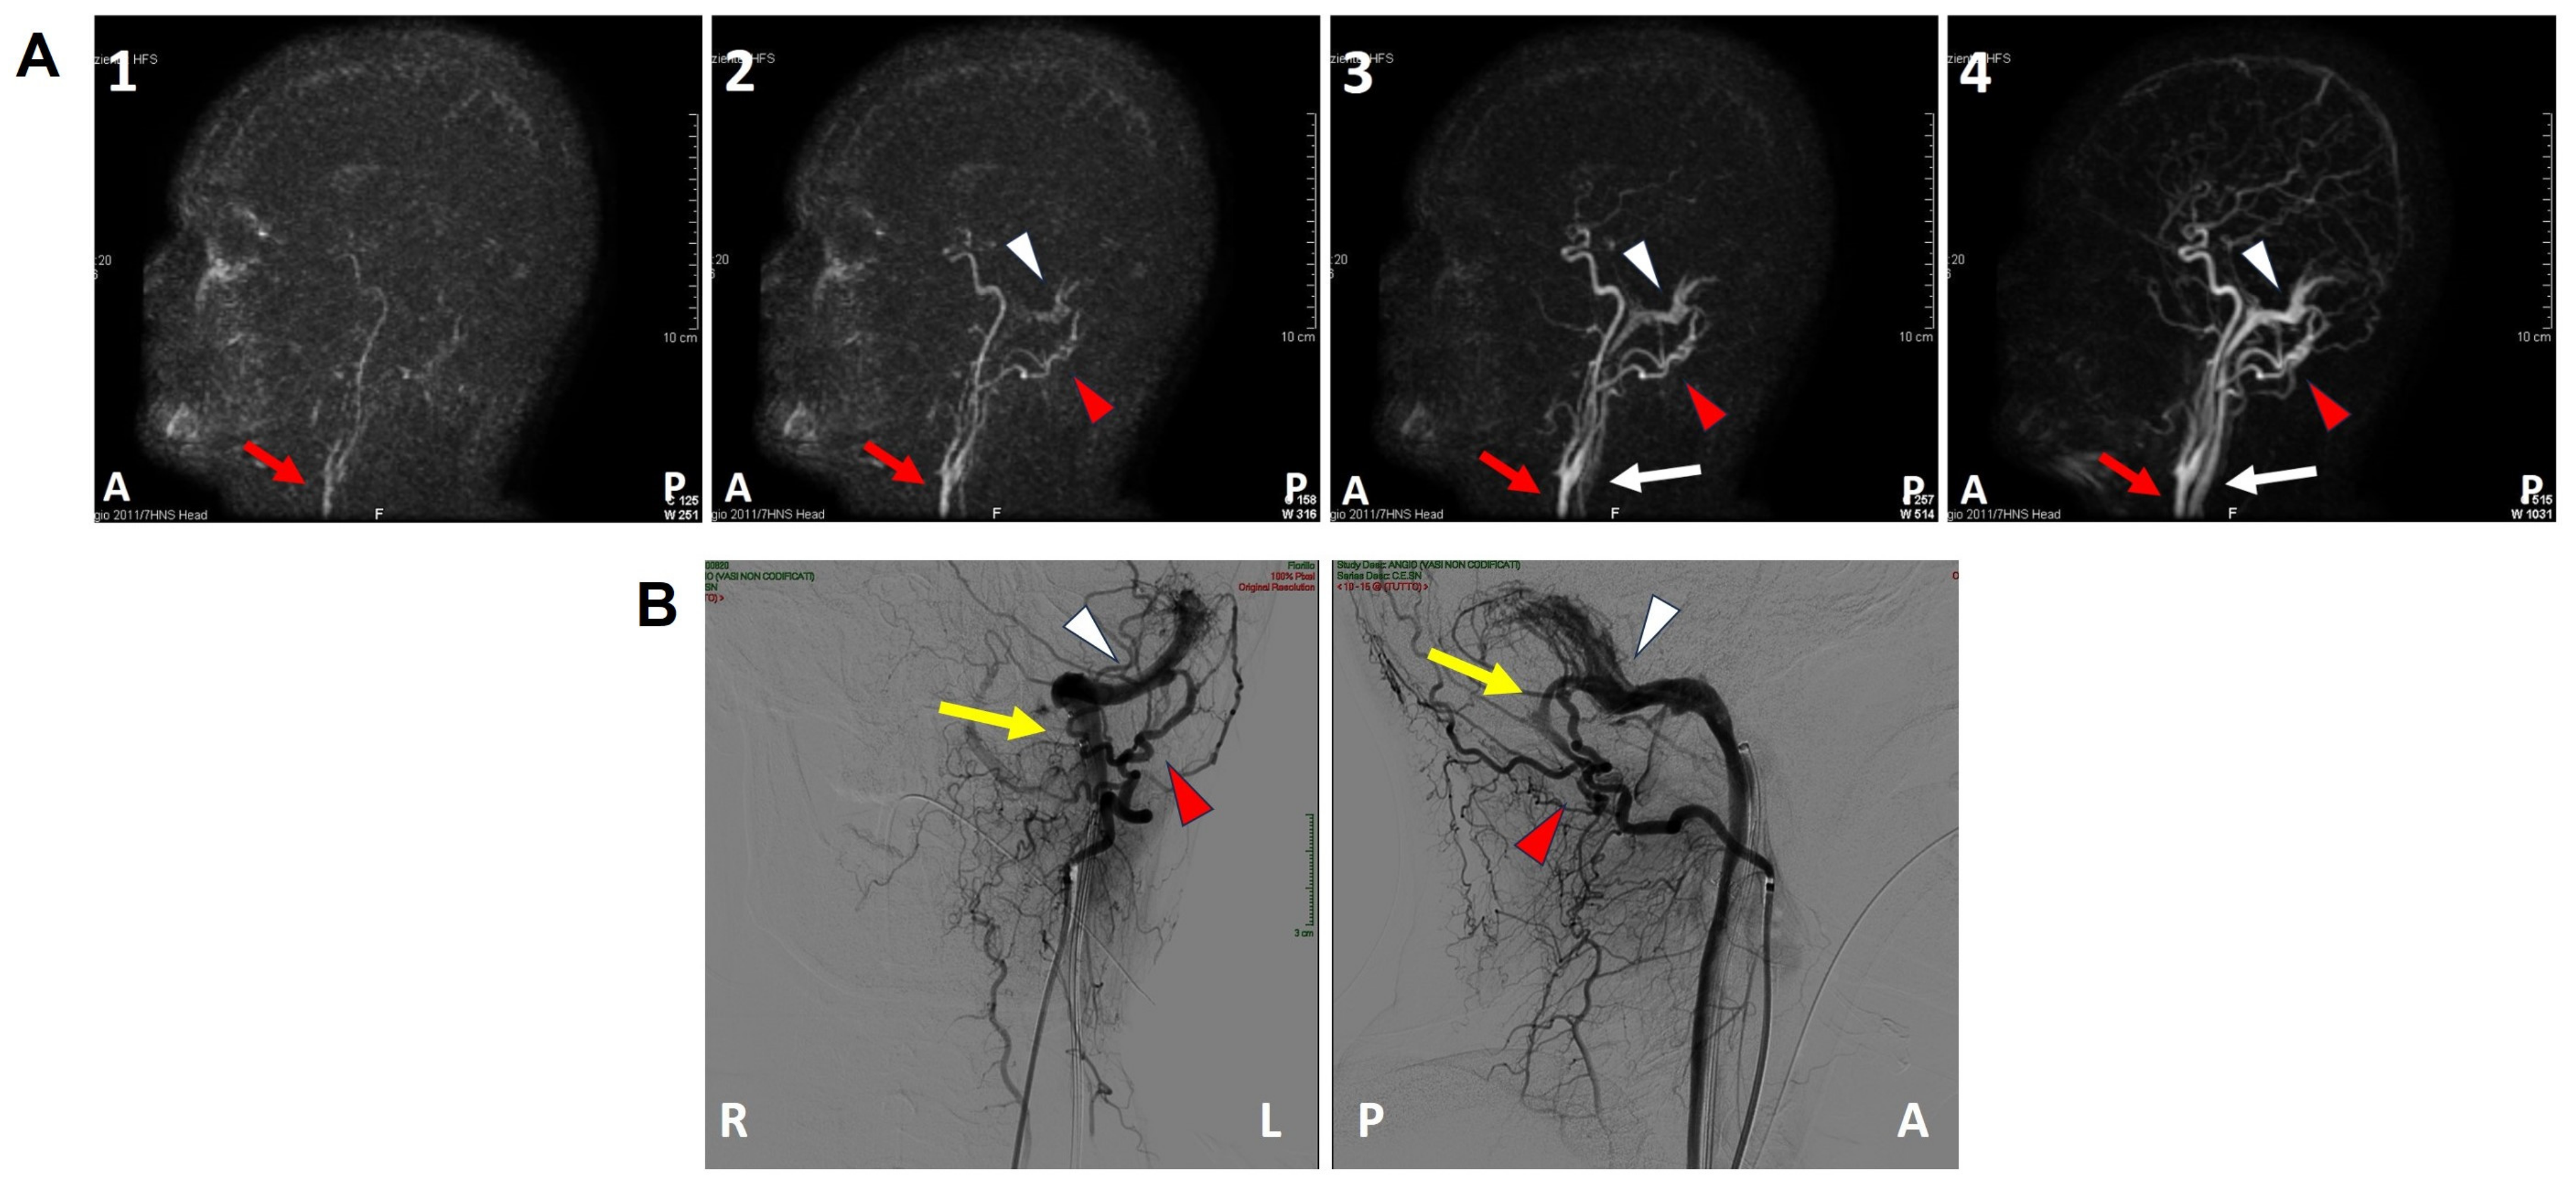

Figure 3.

Pre-operative imaging. (A(1–4)) Brain angio-MRI sequences on the sagittal plane using the TRICKS protocol showing early enhancement of the left dural transverse sinus (white arrowhead). The red arrow indicates the carotid artery trunk, the red arrowhead the left occipital artery and the white arrow the internal jugular vein. (B) Coronal (right side) and sagittal (left side) projections of the intracranial DSA showing a type-I DAVF (yellow arrow) between the left occipital artery (red arrowhead) and the dural transverse sinus (white arrowhead). A: anterior, DSA: digital subtraction angiography, L: left, MRI: magnetic resonance imaging, P: posterior, R: right, TRICKS: time-resolved imaging of contrast kinetics.